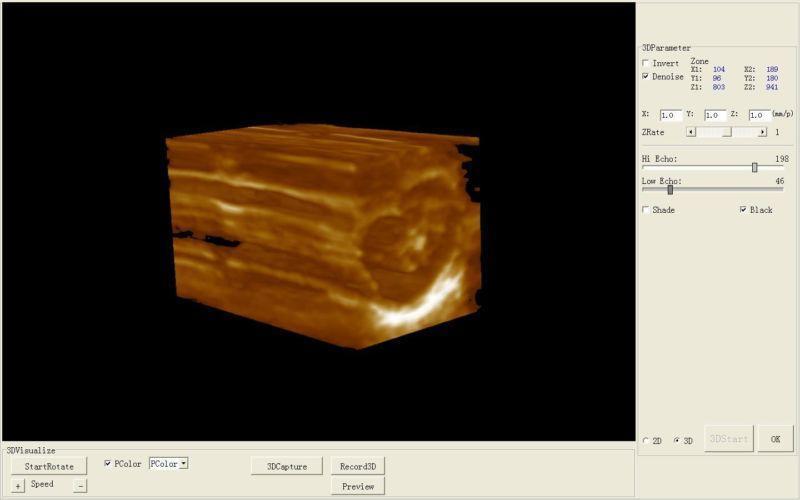

Model: HIGH RESOLUTION

Display modes: B, B+B, B+M, M, 4B

Cline-loop: maximum 128 frames

Permanent Image storage: 32 frames